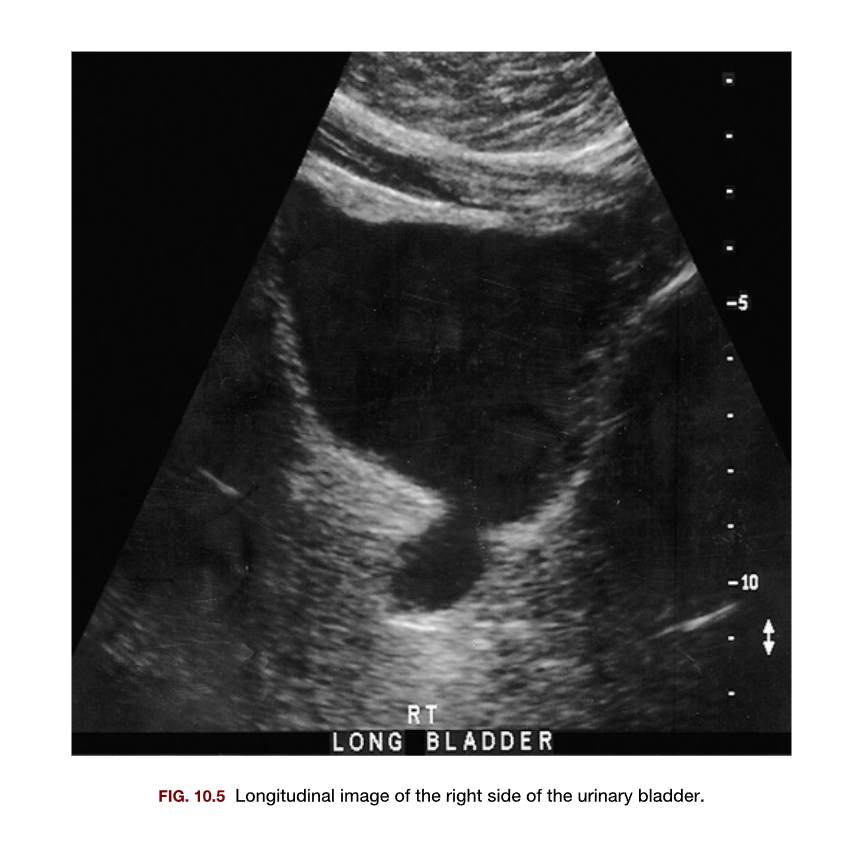

The pathology identified in this sonogram is most suspicious for a

1. Ureterocele

2. Malignant tumor

3. Dilated urethra

4. Bladder diverticulum

A

1. Bladder diverticulum